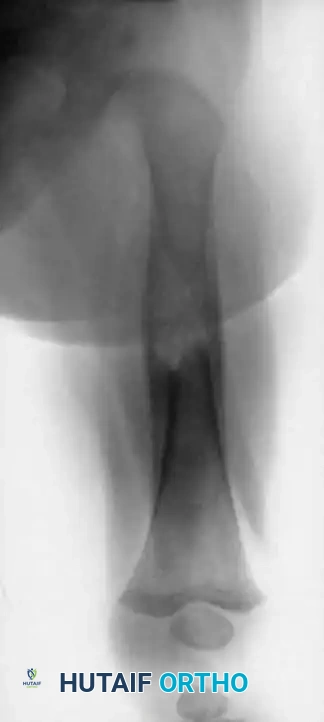

A 4-year-old boy with a 1-year history of right leg pain and antalgic gait. The right tibia was 2 cm longer than the left. Radiographs and CT reveal a lesion in the distal metaphysis causing bowing of the fibula, indicative of a chronic, benign process. The typical microscopic appearance confirms osteoblastoma.

Outside the spine, the radiographic appearance is highly variable and often non-specific. Lesions may be diaphyseal or metaphyseal, intramedullary or cortical, and can appear radiolucent, sclerotic, or mixed. The classic presentation of a calcified central nidus surrounded by a radiolucent halo and reactive sclerosis is occasionally seen.